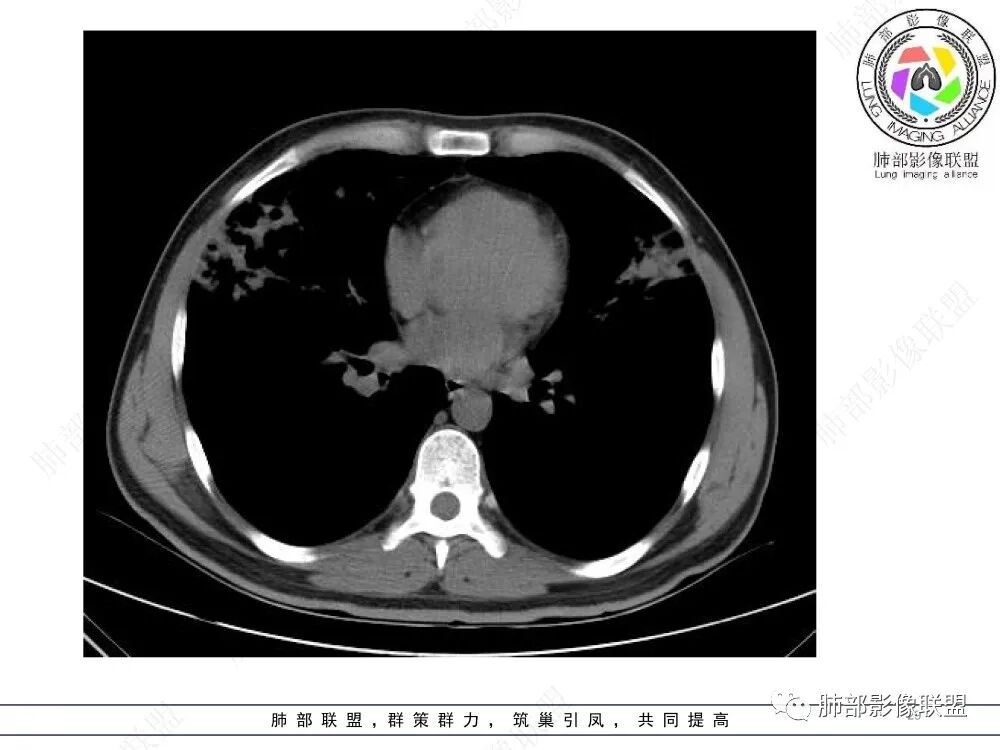

中年男性,慢性咳嗽,有吸烟史,胸部CT基础尚可,双肺多发的沿支气管播散的树芽影以及支气管管壁的增厚和对应区域内的斑片影实变影,符合气道播散的表现。经过对症抗感染治疗1月之后,胸部CT影像进展。右侧播散到左侧。实变和漱牙以及气管壁增厚均较前明显进展。

2.胸部CT:两肺广泛的支扩,支气管壁增厚,多发的树芽影,部分伴有支气管周围的渗出,少量实变。不足一月复查,原有支扩、支气管壁增厚基础上伴有大量渗出,实变,结节,胸膜下累及。

3.综合分析:首先病灶沿支气管分布,呈树芽征及实变影,相应支气管壁广泛增厚,其次病变范围比较广泛,几乎累及所有叶段,这种表现常高度提示气道播散,经过对症抗感染治疗20多天后,胸部CT影像明显进展。符合IPA的进展表现。